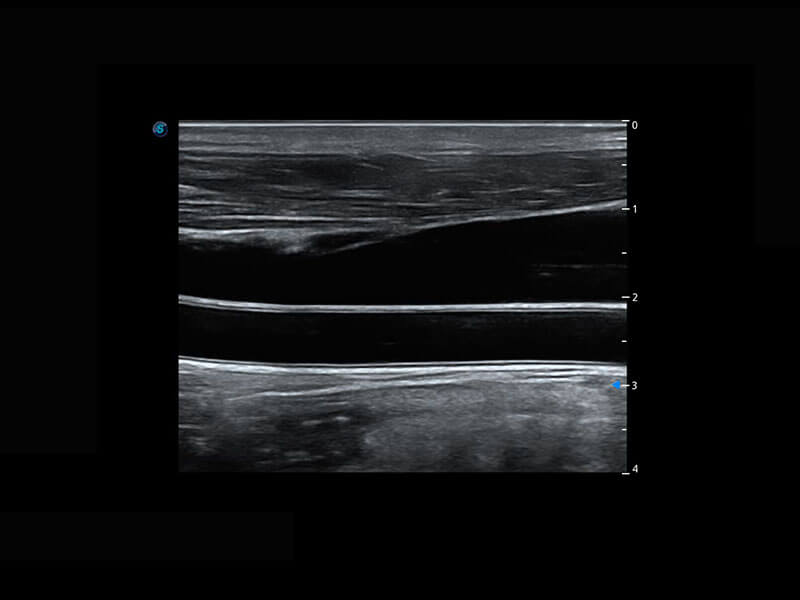

P60搭載寬頻帶線(xiàn)陣探頭、寬景成像、彈性成像技術(shù),為您提供乳腺應(yīng)用方案。P60支持高頻相控陣探頭、線(xiàn)陣探頭、腹部高頻探頭、腹部微凸探頭等,豐富的探頭群搭載敏感的彩色血流成像,適用于新生兒多種臟器檢測(cè)要求,滿(mǎn)足新生兒篩查需求。

新生兒脊髓圓錐